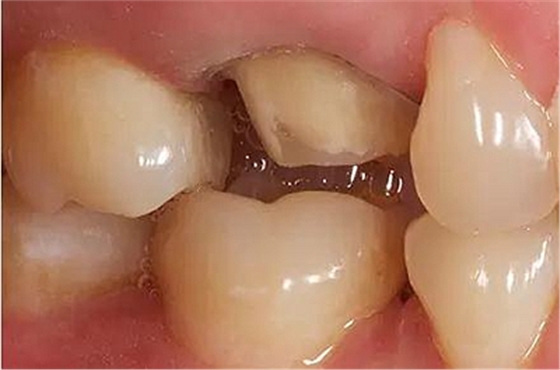

步驟3

牙體制備完成后的牙合面觀

牙合面觀察牙體預(yù)備之后的情況。

軸壁按要求預(yù)留0.8 mm 寬度。

步驟4

咬合間距

與對(duì)牙合牙的咬牙合面間隙至少保留: 1.0 mm 點(diǎn)隙裂溝處的距離,1.5 mm 牙尖高度的距離。